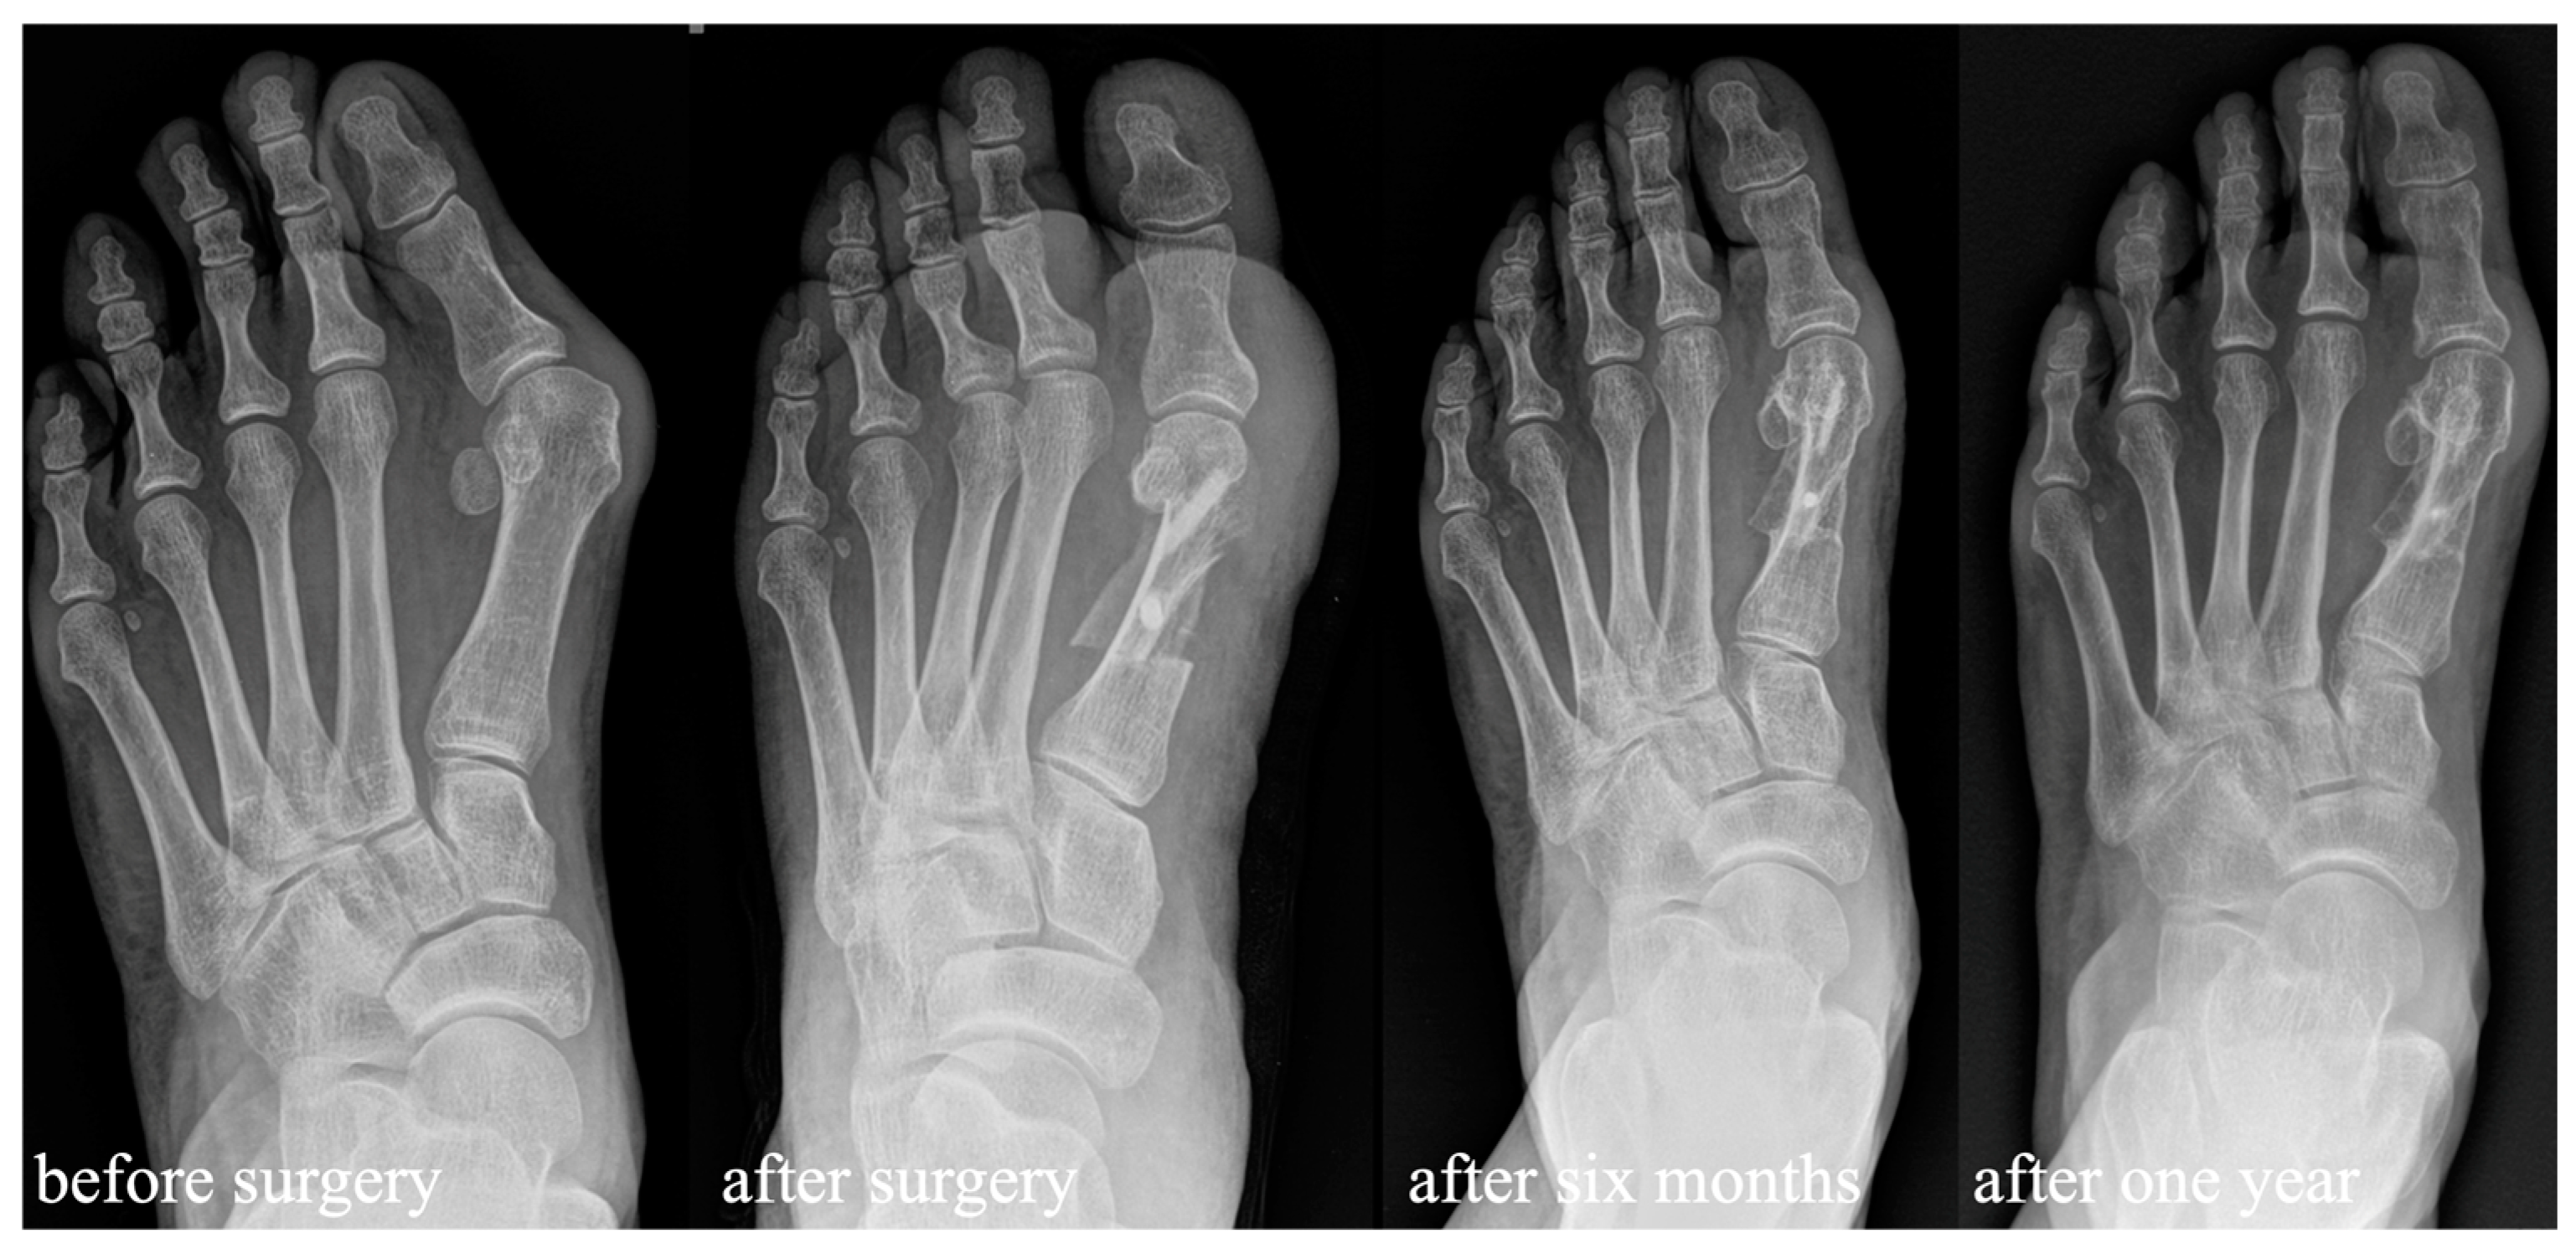

3.1. Clinical and Radiological Outcomes after Scarf Osteotomy Using Allograft Bone Screws

3.2. Comparison of the Usage of Allograft Bone Screws to HCS for Scarf Fixation